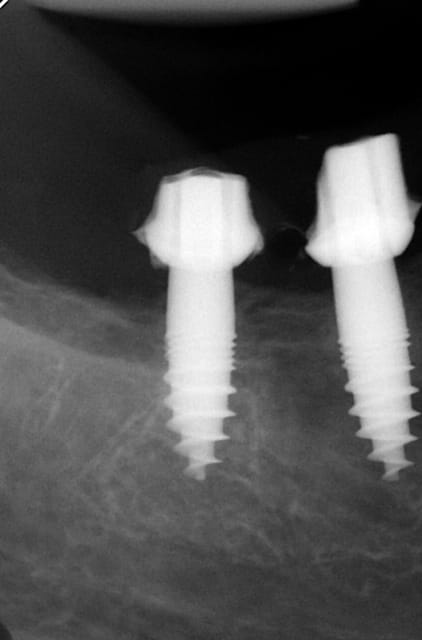

pour répondre à ta question : depuis 1994 , oui d ailleurs dans un des cas présentés tu as une radio après 10 ans :-)! (46 47 )

Maintenant concernant la demande de scans : je poste ce cas, une patiente vient me voir avec son scan car elle a consulté d'autres "spécialistes" et on lui refuse la pose d'implant secteur 4 où alors avec greffe préalable..Ca se discute..pas de temps à perdre je sais faire autrement..

Avec la chir trans gingivale technique MIMI ( Oui..un post sur la technique bientôt ..) j'ai pu placer deux 3,5/8mm..aurai je eu le meme résultat avec un lambeau..j'en doute..Les couronnes sont en titane. Recul clinique 2 ans ras. Simple efficace rapide moins onéreux satisfaisant pour le praticien et la patiente..